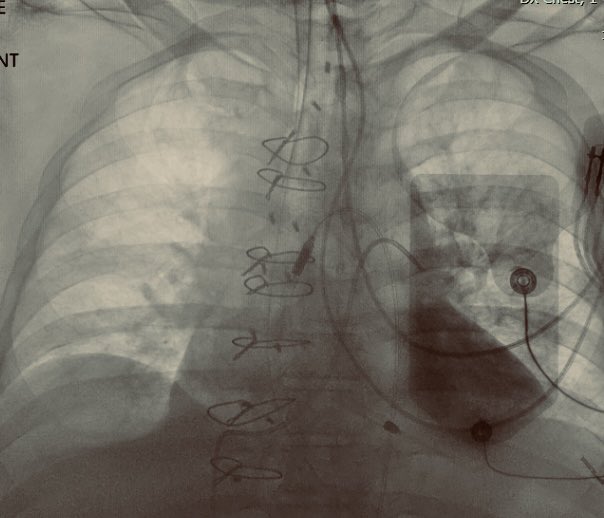

[1] A "wandering" PA catheter

A pt with acute on chronic HFrEF (decline d/t acute ant wall MI) was...

[1] A "wandering" PA catheter A pt with acute on chronic HFrEF (decline d/t acute ant wall MI) was admitted to ICU overnight. Cath lab #hemodynamics: PA 50/27/mean 35, Wedge 27....